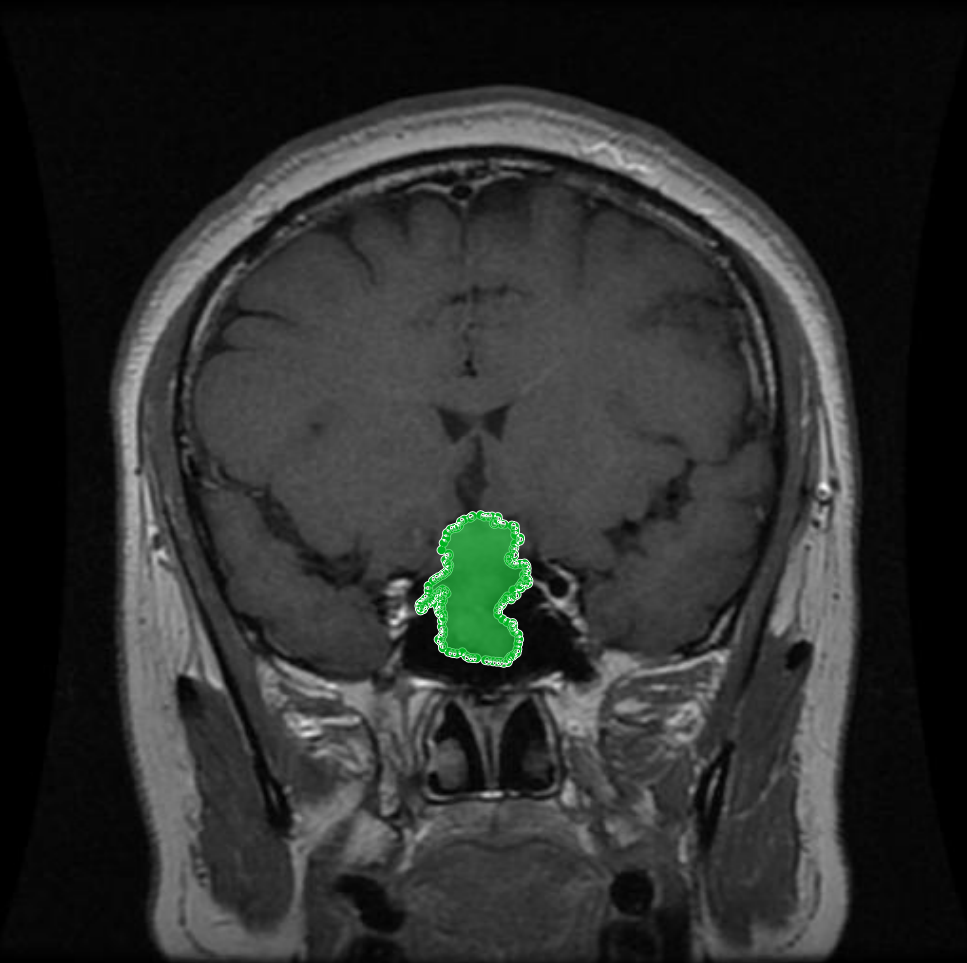

Figure 1: Samples of Glioma segmentation across different imaging planes

Glioma: Gliomas are irregularly shaped and often infiltrate surrounding tissues, presenting significant challenges for precise boundary definition. These complexities require robust segmentation techniques to capture their variable morphology. As shown in Figure 1, gliomas exhibit irregular and diffuse growth patterns, which are highlighted through annotated tumor masks.

The original collection contains 7,023 brain MR images across four classes: glioma, meningioma, pituitary tumour, and non-tumorous (the latter sourced from Br35H). We then applied the following steps to ensure consistency and quality: Original Image Binary Mask Tumor Region Overlay Axial